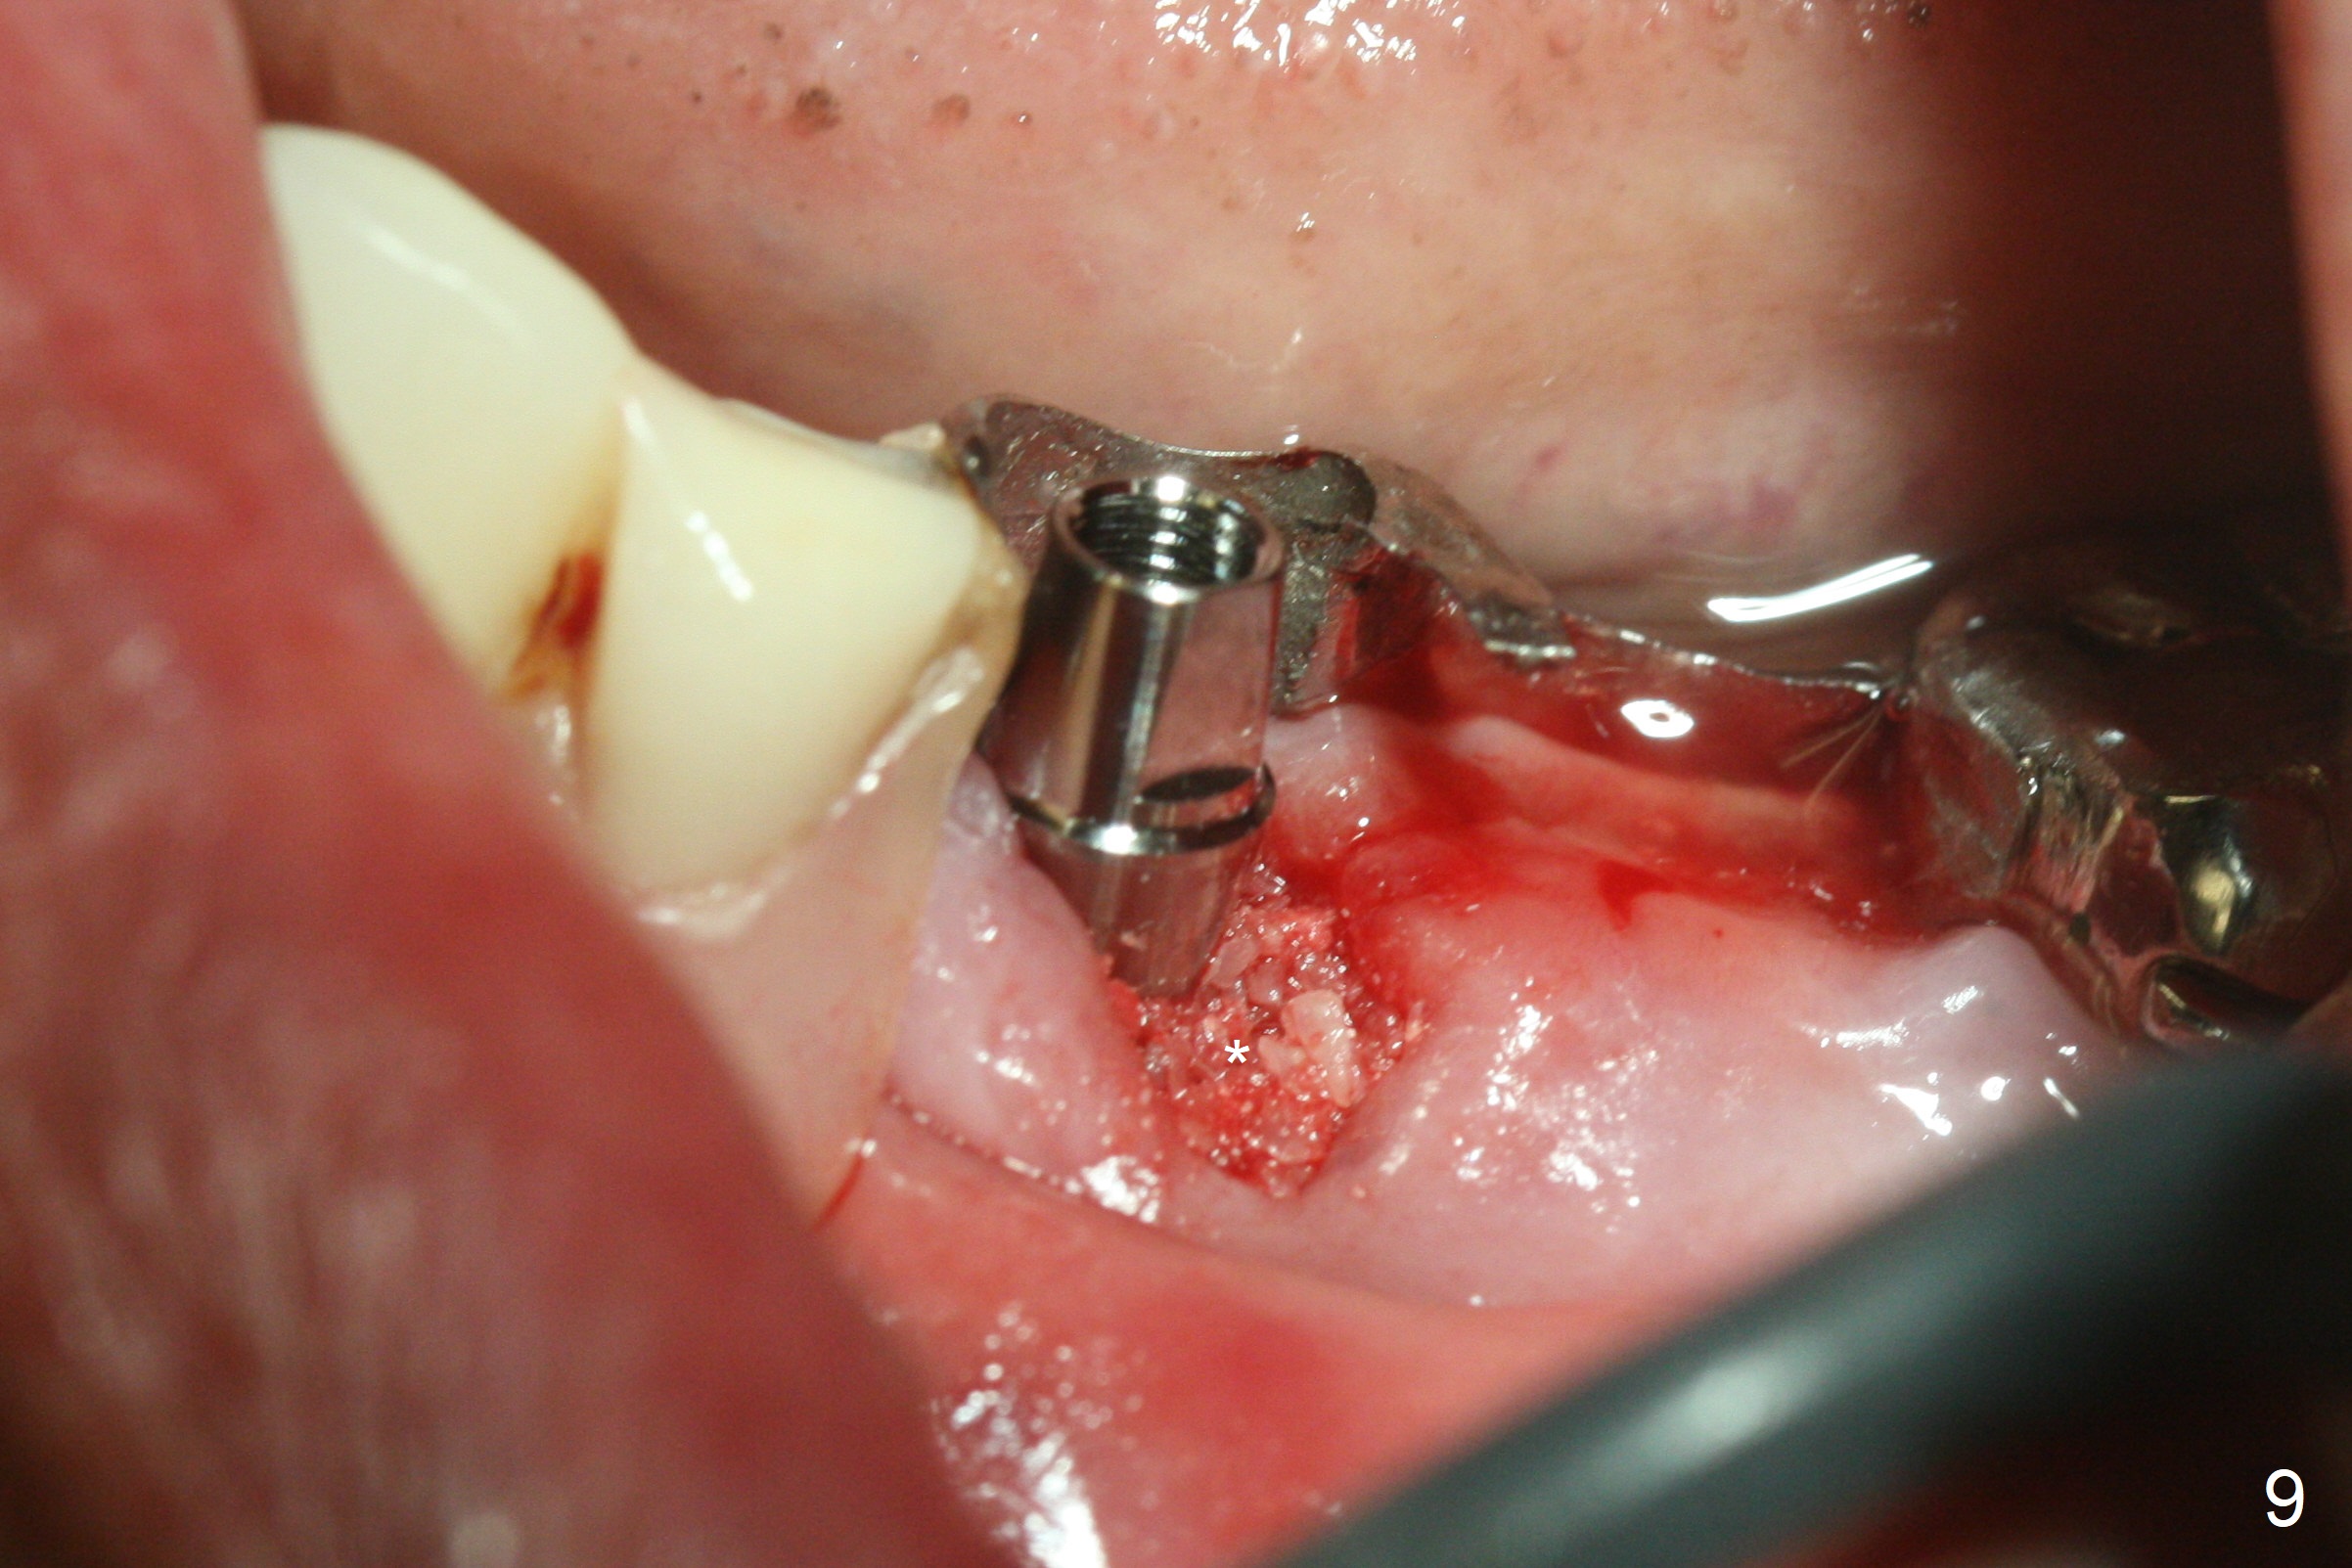

After removal of the pontic at #19 and retainer at #20 (Fig.1) and of vertically fractured root, the buccal plate is found to be defective (Fig.2 *). An implant will be placed as lingual as possible. Since the apex of the affected tooth is coronal to the Mental Loop (Fig.3 red dashed line), an osteotomy (Fig.4 yellow arrow) to be established in the mesial slope (blue dashed line) after extraction (black area) appears to be safer than that along the long axis of the tooth. The initial osteotomy is accomplished by free hand (Fig.5), but when the lower RPD is inserted, the superior end of the 1.5 mm pilot drill is distal (Fig.6). When the trajectory is corrected using the RPD as a surgical guide at the same depth (17 mm gingival level), brisk hemorrhage is from the osteotomy without severe pain. After hemostasis is achieved by packing the socket with Osteogen plug and bone graft and packing bone graft into the osteotomy, 3.3 mm Magic Drill is used for 14 mm. A 4x11 mm IBS implant is placed with 60 Ncm (Fig.7). The implant is then placed deeper, followed by placement of a 4.5x4(3) mm abutment and further bone graft (Fig.8). Finally the implant/abutment complex is apparently in an acceptable mesiodistal position with a large buccal gap which has been filled by bone graft (Fig.9 *). In fact the Mental Loop seems to have been not violated in the procedure (Fig.10). X-ray is taken 3 and 6 months postop. Bone graft (Fig.11,12 (CBCT) *) appears to remain over the buccal (B) surface of the implant coronally 13 months postop (7 months post cementation). The gingiva at #19 and 20 is apparently healthy 8 months post cementation except mild recession at #20 (Fig.13).